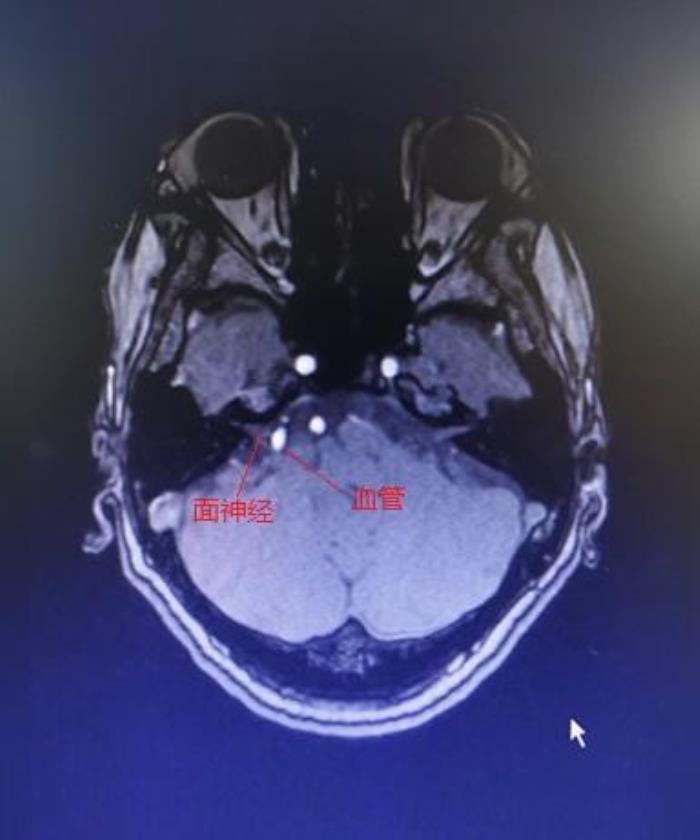

这是MRI增强,可见强化的白色血管压迫面神经

1.头部磁共振(MRI)及CT

CT及MRI可以发现颅内肿瘤、面神经受压等病变,是面肌痉挛的首选检查。